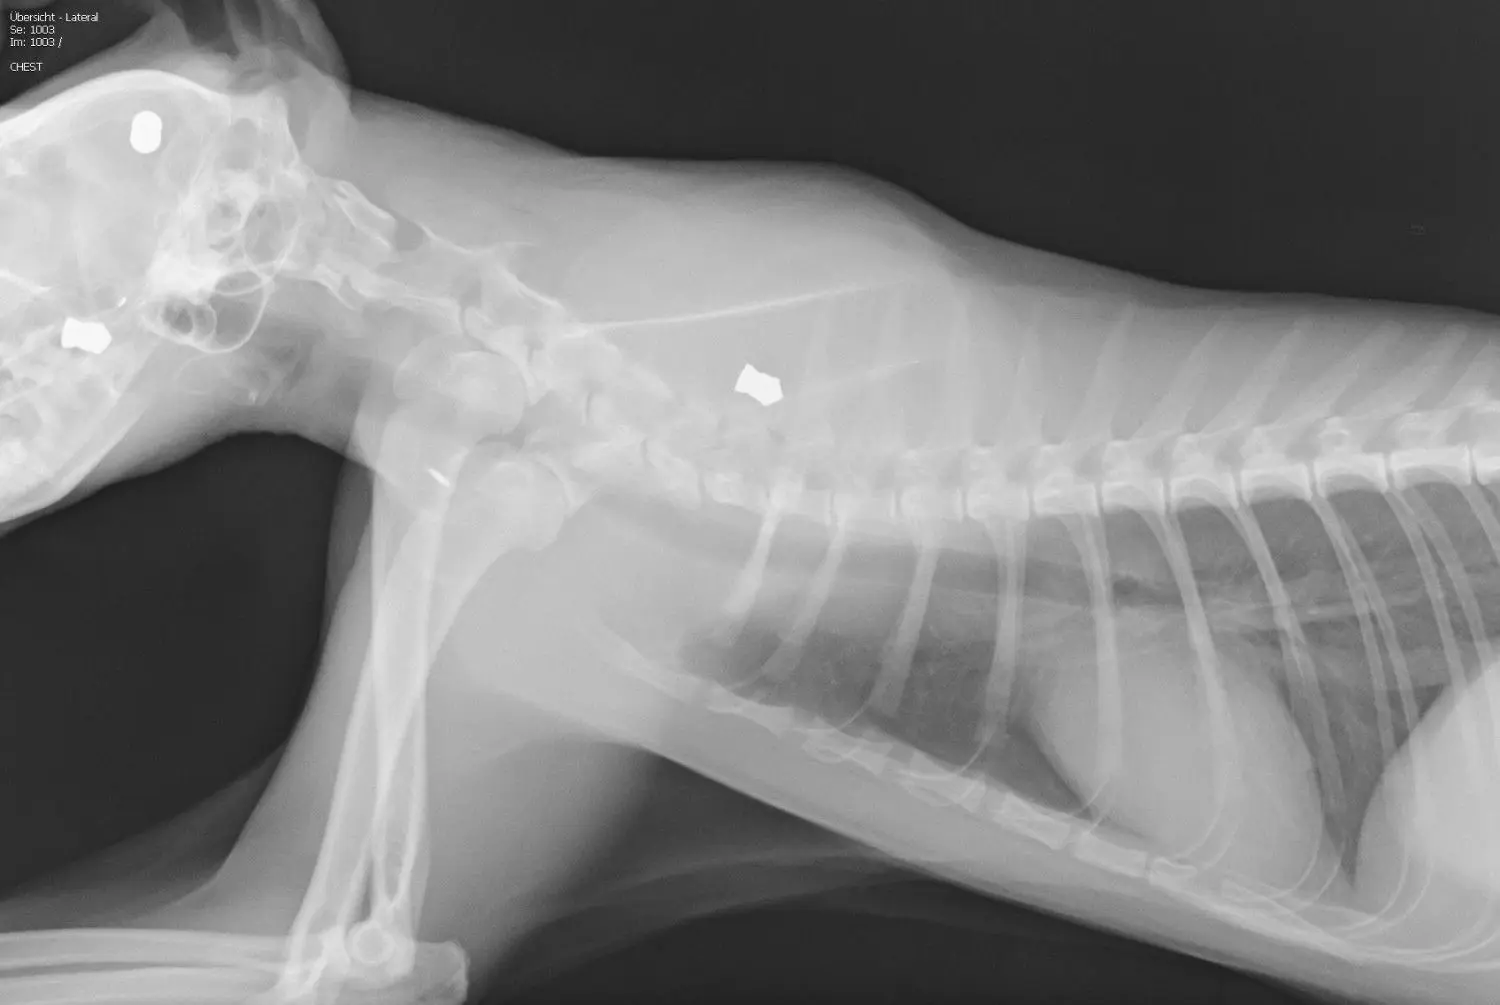

• Auf dem Röntgenbild von Kater Tarzan sind drei Projektile zu sehen. Zwei stecken im Kopf, eins in der Schulter, kurz vor der Wirbelsäule.

Auf dem Röntgenbild von Kater Tarzan sind drei Projektile zu sehen. Zwei stecken im Kopf, eins in der Schulter, kurz vor der Wirbelsäule.